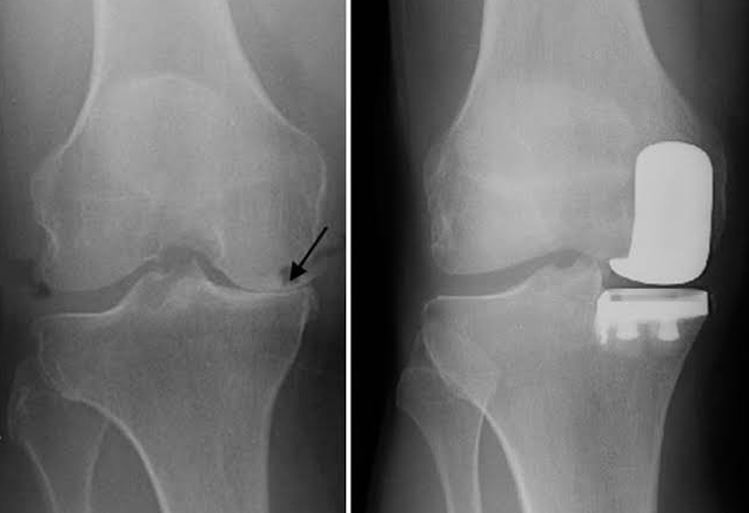

Unicompartmental (Partial) Knee Replacement

In knee osteoarthritis, the cartilage protecting the bones of the knee slowly wears away. This can occur throughout the knee joint or just in a single area of the knee.

Advanced osteoarthritis that is limited to a single compartment may be treated with a unicompartmental knee replacement. During this procedure, the damaged compartment is replaced with metal and plastic. The healthy cartilage and bone, as well as all of the ligaments, are preserved.

Partial Knee Replacement